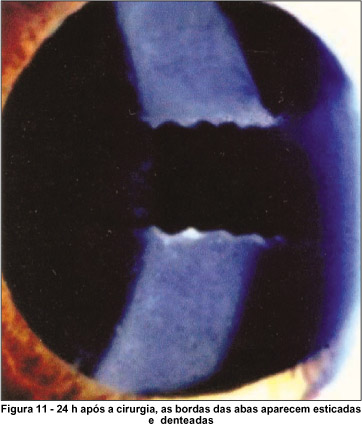

No que se refere ao comportamento das abas da cápsula anterior, notou-se que, durante os primeiros dias do período pós-operatório, tais elementos se apresentavam perfeitamente esticados sobre a lente intra-ocular. Suas bordas apareciam denteadas, em conseqüência das puncturas realizadas durante a capsulotomia anterior (Figura 11). Algumas vezes (20 casos - 26,6%), essas bordas se apresentavam retas, por terem os seus dentes se dobrando, no decorrer da cirurgia.